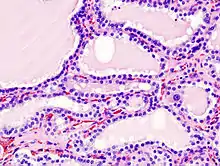

Hyperthyroidism is one of the most common endocrine conditions affecting older domesticated housecats. In the United States, up to 10% of cats over ten years old have hyperthyroidism.[59] The disease has become significantly more common since the first reports of feline hyperthyroidism in the 1970s. The most common cause of hyperthyroidism in cats is the presence of benign tumors called adenomas. 98% of cases are caused by the presence of an adenoma,[60] but the reason these cats develop such tumors continues to be studied.

The most common presenting symptoms are: rapid weight loss, tachycardia (rapid heart rate), vomiting, diarrhea, increased consumption of fluids (polydipsia), increased appetite (polyphagia), and increased urine production (polyuria). Other symptoms include hyperactivity, possible aggression, an unkempt appearance, and large, thick claws. Heart murmurs and a gallop rhythm can develop due to secondary hypertrophic cardiomyopathy. About 70% of affected cats also have enlarged thyroid glands (goiter). 10% of cats exhibit "apathetic hyperthyroidism", which is characterized by anorexia and lethargy.[61]